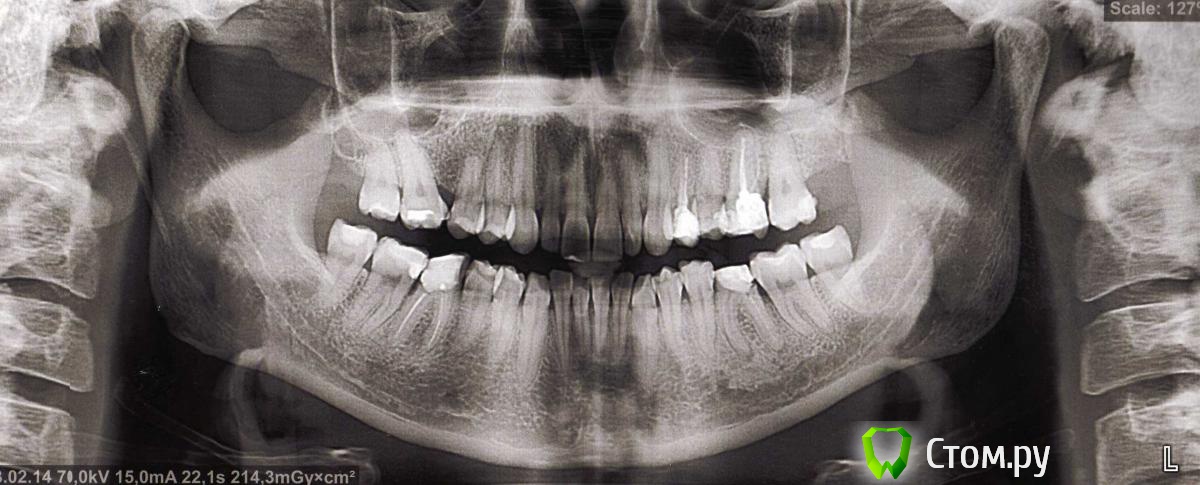

ОлиЯ Опубликовано 13 февраля, 2014 Поделиться Опубликовано 13 февраля, 2014 Была у ортодонта.Сказал не чего не нужно лечить.только удалять 6 снизу. Ссылка на комментарий

red_butler Опубликовано 15 февраля, 2014 Поделиться Опубликовано 15 февраля, 2014 Вам необходим комплексный план лечения, сходите еще на консультации Ссылка на комментарий